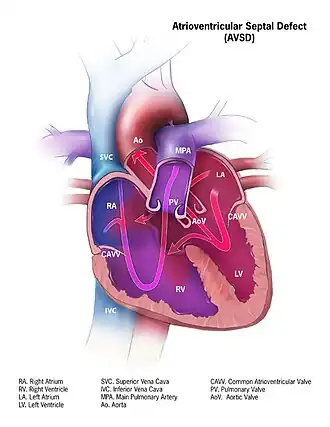

O defeito do septo atrioventricular (DSAV) ou defeito do canal atrioventricular (DCVA), também conhecido como " canal atrioventricular comum " (CAVC) ou " defeito do coxim endocárdico " (ECD), é caracterizado por uma deficiência do septo atrioventricular do coração . É causada por uma fusão anormal ou inadequada dos coxins endocárdicos superior e inferior com a porção média do septo atrial e a porção muscular do septo ventricular .

- No AVSD parcial, há um defeito na parte primum ou inferior do septo atrial, mas nenhuma comunicação intraventricular direta ( defeito do ostium primum ).

- No AVSD completo (CAVSD), há um grande componente ventricular abaixo de um ou ambos os folhetos de ponte superior ou inferior da válvula AV. O defeito envolve toda a área de junção das câmaras superior e inferior do coração, ou seja, onde os átrios se unem aos ventrículos. Há um grande orifício entre a porção inferior dos átrios e a porção superior ou "de entrada" dos ventrículos e isso está associado a uma anormalidade significativa das válvulas que separam os átrios dos ventrículos. As válvulas de fato tornam-se uma válvula atrioventricular comum, e a gravidade do defeito depende em grande parte das ligações de suporte da válvula aos ventrículos e se a válvula permite fluxo dominante do átrio direito para o ventrículo direito e do átrio esquerdo para o esquerdo ventrículo (fluxo "desequilibrado"). Os problemas gerais são semelhantes aos do VSD, mas são mais complicados. Há um aumento do fluxo sanguíneo para os pulmões através dos componentes ventricular e atrial do defeito. Além disso, a válvula atrioventricular anormal invariavelmente vaza, de modo que, quando os ventrículos se contraem, o sangue flui não apenas para o corpo e os pulmões, mas também para os átrios. O efeito da contrapressão nos átrios causa congestão de sangue no átrio esquerdo em particular, e isso por sua vez causa congestão nas veias que drenam os pulmões. O efeito no bebê é piorar a insuficiência cardíaca associada a uma CIV isolada e acelerar o aparecimento de hipertensão pulmonar. Deve-se mencionar que o CAVSD é encontrado em aproximadamente um terço dos bebês com síndrome de Down, mas também ocorre como uma anormalidade isolada.